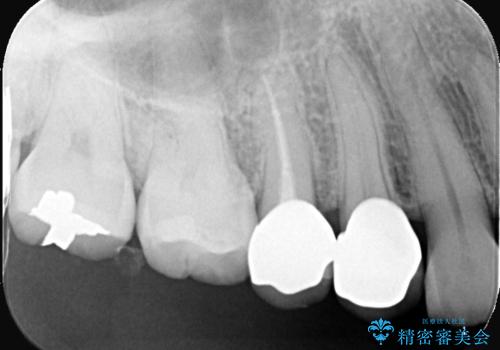

残存歯質を最大限に温存しつつ、フェルールを確保できるよう慎重に形成を行いました。

その後、型取りを行い、精密に適合するセラミッククラウンを作製しました。

クラウンの装着時には適合状態を確認し、接着操作を丁寧に行いました。

治療後は審美性と機能性の両面で良好な状態が得られ、患者様にもご満足いただけました。